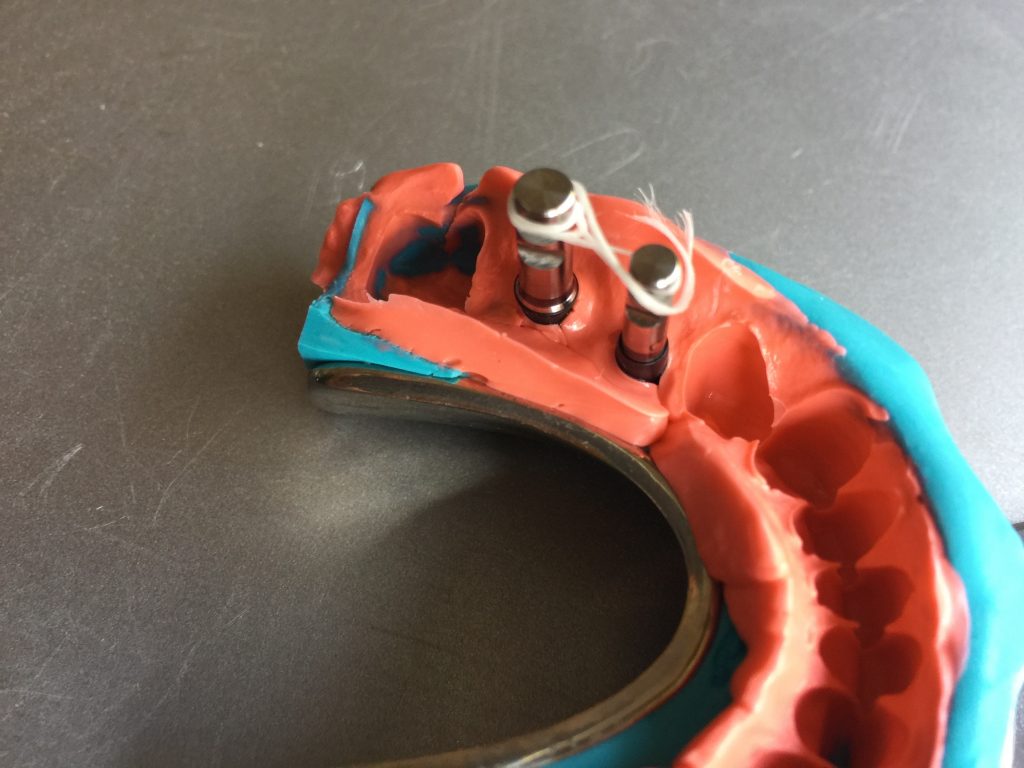

Autores: PRÓLOGO Asimismo, desde el punto de vista pedagógico, el profesional nobel en la materia tiene a su alcance la posibilidad de corregir cualquier posición implantaría en el ordenador, planear los provisionales y plasmarlos en la bio réplica antes de tocar al paciente a operar. Todos estos razonamientos nos llevan a presentar un caso de condiciones muy favorables para poner en práctica estos métodos como primer acercamiento a una Odontología Digital de alta calidad, con medios informáticos, que ya están presentes en la profesión de hoy en día, y será la protagonista única del futuro. Por otro lado, después de numerosos estudios que nos llevan a plantear el “gap” entre implante y pilar(abuttment), como principal responsable de la periimplantitis dado que la microbiota presente en el mismo es imposible de limpiar y en su presencia la cortical ósea reacciona reabsorbiéndose, nos ha llevado a utilizar implantes monobloc ya que los ejes implantarios y protéticos coincidían, y nos permitían su uso. Además, el circonio, ha mostrado a la luz de estudios muy recientes, una preservación y adhesión de los tejidos blandos superiores al titanio, tanto en su tratamiento de superficie de la rosca como a nivel gingival. DESARROLLO Paciente varón de 68 años, con antecedentes de radio/quimioterapia cinco años antes, con Rehabilitación Oral de los cuatro cuadrantes, con una Oclusión Mutuamente Compartida conservada, (REF.8) la que fracasa en el cuadrante 4, 19 años después. El mismo presentaba un puente de porcelana sobre circonio con pilares en 44 y 47, reemplazando el edentulismo de 45 y 46. Se produce la fractura del PM del 44, y ante una endodoncia antigua y corta, se decide implantar las zonas edéntulas, conservando temporariamente los pilares, hasta producida la oseointegración, para entonces también exodonciar el 44. DIAGNÓSTICO Tomamos impresiones del maxilar antagonista, Arco Facial Estático y realizamos montaje del mismo mediante la sistemática ARTEX. Producimos la relajación del músculo Pterigoideo Externo, para obtener la ORC (Oclusión en Relación Céntrica) mediante el método de Laminillas de Long, basado en el concepto de INERVACIÓN RECÍPROCA. Esto nos permitirá montar el maxilar inferior, tanto en su forma de: La primera para practicar la cirugía guiada y comprobar su eficacia, y el modelo de yeso para ser escaneado y confeccionar la GUÍA QUIRÚRGICA. La Biorréplica la obtenemos transformando los archivos DICOM que nos da el CBCT en archivos STL, y a partir de ellos, mediante una tecnología de PROTOTIPADO RÁPIDO, la obtención de un objeto físico en 3D a través de la aglutinación selectiva de una sucesión de capas de polvo. Procedemos a montar la biorrèplica y el modelo de yeso del caso. Podemos verificar la exactitud de las medidas del hueso residual en la bio réplica y compararlas con el scanner. Arrojando un resultado de 8,5 mm de cortical externa a cortical externa. Pudiendo también medir la distancia hasta el dentario. y comparar gracias a la ventana lateral de la biorréplica Dándonos 22mm de distancia. Con lo cual deducimos que implantes de 4,1mm por 12 mm serán perfectamente rodeados de hueso. Medimos también la distancia desde oclusal del antagonista, hasta el hueso desnudo. Lo mismo que, mediante la utilización de la guía radiológica, con un material radiolúcido colocado en gingival de la misma, podemos medir la altura de la encía. Con lo cual podemos calcular la altura del pilar. Es entonces cuando con el programa COC Diagnostix se realiza la programación final: Obteniendo no solo la ubicación, largo, ancho y ángulo de los implantes sino también los provisionales mediante CAD CAM. Ya entonces podemos hacer la práctica quirúrgica en la bio réplica, mediante la guía quirúrgica, instalando los implantes de prueba que no serán los de circonio, ya que la casa no cuenta con ellos, pero si otros de las mismas dimensiones. TRATAMIENTO Entramos ya en la cirugía propiamente dicha. Antisepsia de la zona a operar y zonas anexas. Comprobación del perfecto ajuste e inmovilidad de la G.Q. en boca durante la cirugía. Marcado de la encía y perforación de la cortical. Visión a través de la Guía de la mínima intervención anterior. Comprobación sin Guía. Incisión mínima mesio distal, para apartar y conservar encía queratinizada. Secuencia de drills, perforando a profundidad requerida Observación del Mínimo Trauma Implantes Strauman de Zirconio Monoblock en blíster y montádo en contrángulo reductor. Instalación controlando torque con contrángulo reductor. Comprobación clínica. Comprobación Radiográfica y con Guía. Toma de impresiones, y armado de modelos con técnicas de pasividad protética. Montaje. Resultado de las provisionales ejecutadas por CAD CAM Al no estar conformes con el resultado decidimos desechar dichas provisorias y optar por repetirlas. Nuevas provisorias realizadas mediante encerado convencional. Estado de los tejidos blandos. Provisorias en boca. Oclusión de Estímulo Inmediato. Ref.10: Carga inmediata .Alberto y Diego Bechelli. Comprobación mediante CBCT post operatorio Componentes del equipo (En la próxima presentación, mostraremos las coronas definitivas de porcelana sobre circonio, y la desoclusión provocada por una OCLUSIÓN MUTUAMENTE COMPARTIDA, sobre estos implantes y otros seis mas) REFERENCIAS

A-BIORRÉPLICA

B-MODELO DE YESO

FIG: 14-15-16-17-18-19-20

Fig. 14

Fig. 15

Fig. 16

Fig. 17

Fig. 18

Fig. 19

Fig. 20